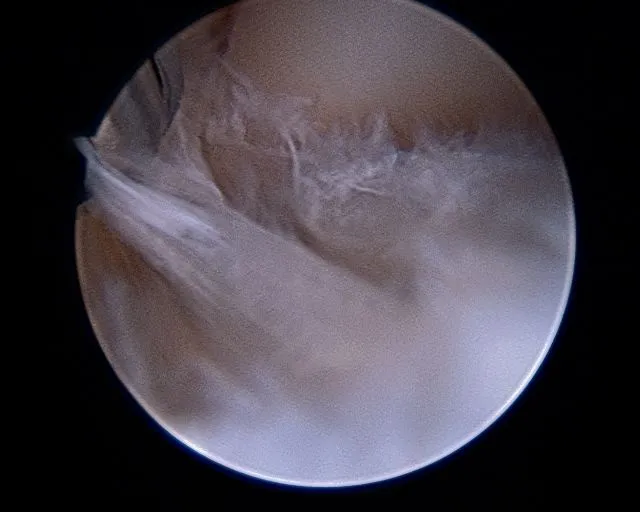

Intraoperative subtalar joint arthroscopy pics

Scar tissue and fibrous band in the subtalar joint

Cleaning out the joint